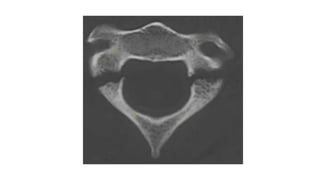

Axial load on straight C- spine

Force: Vertex → Occipital condyles → Lateral masses

of 𝐶1

• 4 part fracture

2 anterior arch fractures

2 posterior arch fractures

• Decompressive fracture

Stable

<4 part fracture

Asymmetrical axial load

Rupture of Transverse ligament

• #34 For true jeff Force hits the vertex of the head, go down through the occ condyles land on c1 and drive c1 to sides and disperse the fragments radially

• #37 Any tilt on the neck when the force is being applied